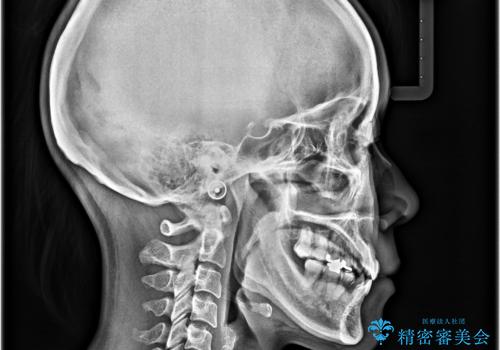

- 学生時代に行った抜歯矯正の後戻りで、隙間ができてしまったことを気にして来院された患者様です。

マウスピース矯正を検討されていましたが、後戻りの隙間が非常に大きく、奥歯を前方に移動させる必要があるため、ワイヤー装置にて矯正治療を行うこととしました。

舌の突出癖が非常に強く、その影響で隙間ができてしまったので、舌のトレーニングをしっかりと行っていただきました。